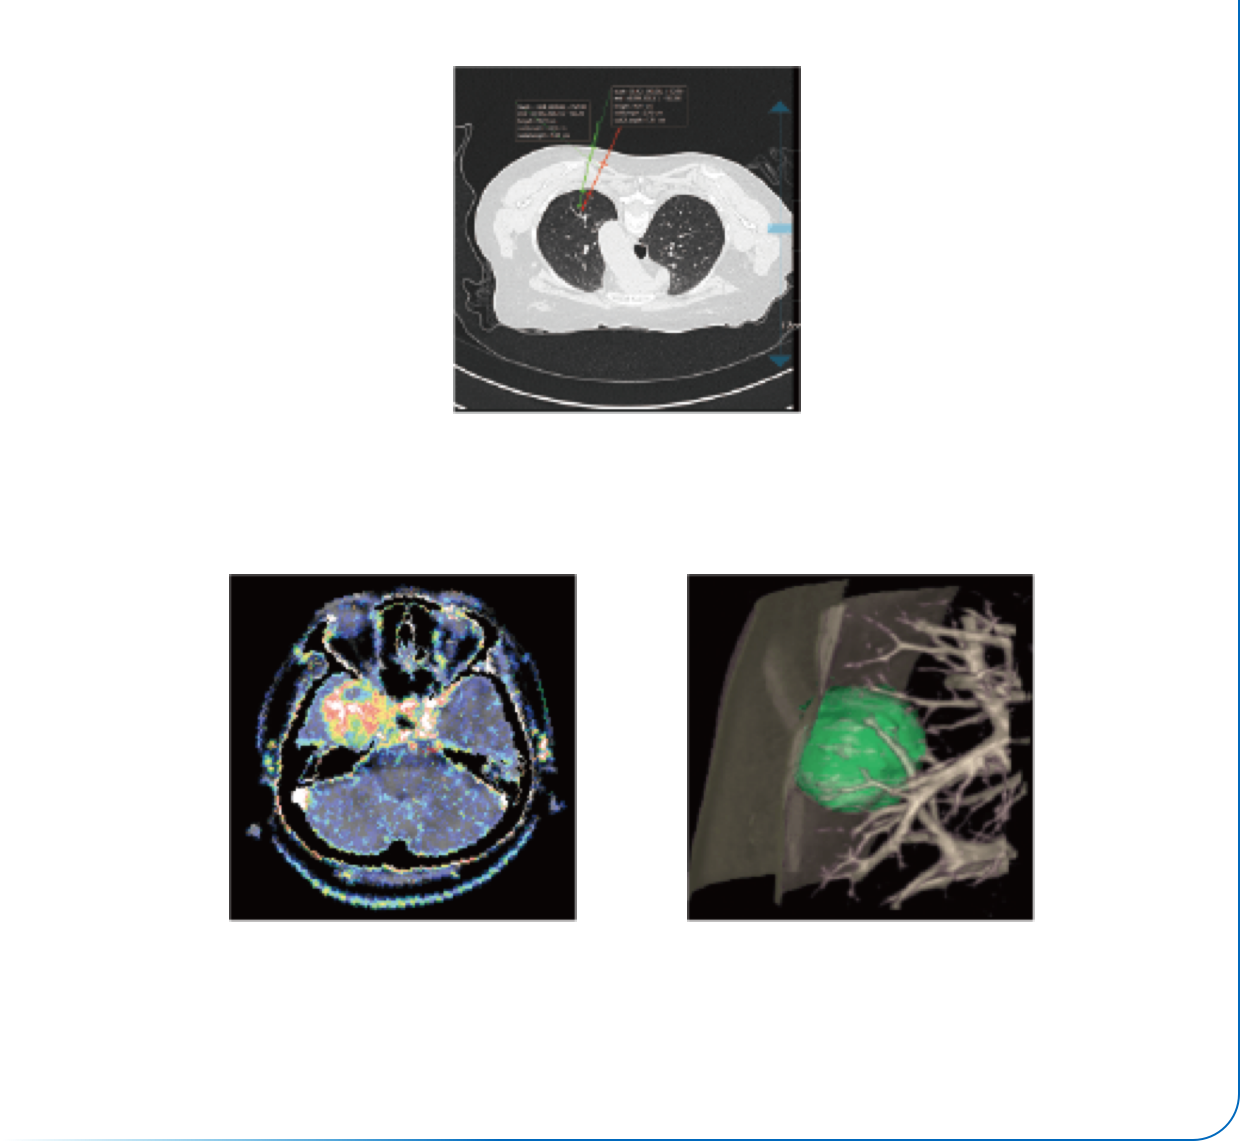

内置心电显示

精准ECG-DOM剂量调制

智能门控扫描

智能心律识别

智能期相选择

智能扇区重建

智能冠脉运动伪影补偿